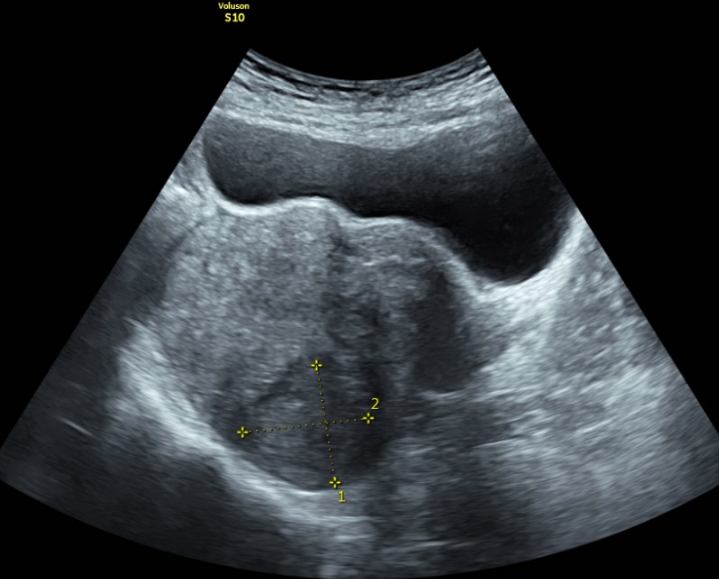

Trong thăm khám phụ khoa đối với nữ giới, siêu âm tử cung phần phụ là phương pháp chẩn đoán hình ảnh được áp dụng phổ biến, giúp đánh giá chức năng sinh sản, xác định niêm mạc tử cung dày hay mỏng và tầm soát một số bệnh phụ khoa.

Hiện nay, sự ra đời của kỹ thuật siêu âm giúp bác sĩ quan sát được bờ ngoài của tử cung bình thường có hình quả lê, khoang nội mạc có hình tam giác được cấu tạo bởi hai sừng và một cổ tử cung. Tử cung bình thường có bờ nội mạc vùng đáy lồi hoặc phẳng.

Siêu âm tử cung phần phụ được dùng để chẩn đoán các bệnh lý ở tử cung, xác định niêm mạc tử cung dày hay mỏng, đánh giá sự phát triển của buồng trứng, phát hiện các dị tật ở tử cung hoặc phát hiện thai ngoài tử cung, từ đó tìm ra nguyên nhân gây vô sinh, hiếm muộn.

Phương pháp siêu âm đầu dò giúp khảo sát tử cung rõ nét hơn qua ngả âm đạo. Bác sĩ sẽ đưa đầu dò vào ống âm đạo và kiểm tra các cơ quan sinh dục như tử cung, cổ tử cung, buồng trứng, ống dẫn trứng, âm đạo thông qua các hình ảnh siêu âm chi tiết thể hiện trên màn hình. Để quá trình siêu âm đạt kết quả tốt nhất, bệnh nhân cần thực hiện theo hướng dẫn của bác sĩ nên để bàng quang trống rỗng hay căng đầy tùy thuộc vào từng trường hợp và lý do siêu âm.